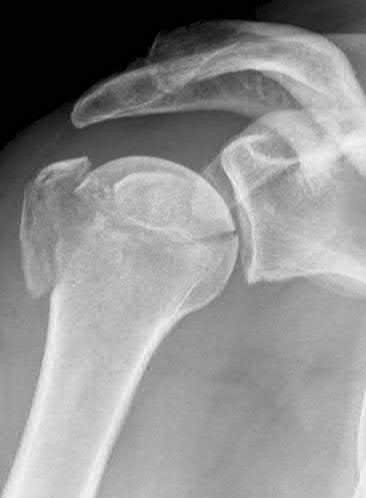

A 45-year-old male presents with a high-energy knee injury. Representative radiographs and CT cuts are shown. Based on the principles of treating a bi-condylar tibial plateau fracture with a posteromedial shear fragment, which surgical approach is most appropriately utilized first to stabilize the medial column?

Correct Answer: Posteromedial

A posteromedial shear fragment in a bicondylar tibial plateau fracture (Schatzker VI or Moore Type I) requires a posteromedial approach for optimal buttress plating. Stabilizing the medial column first via a posteromedial approach converts the complex fracture into a lateral plateau fracture, which can then be addressed via a standard anterolateral approach.